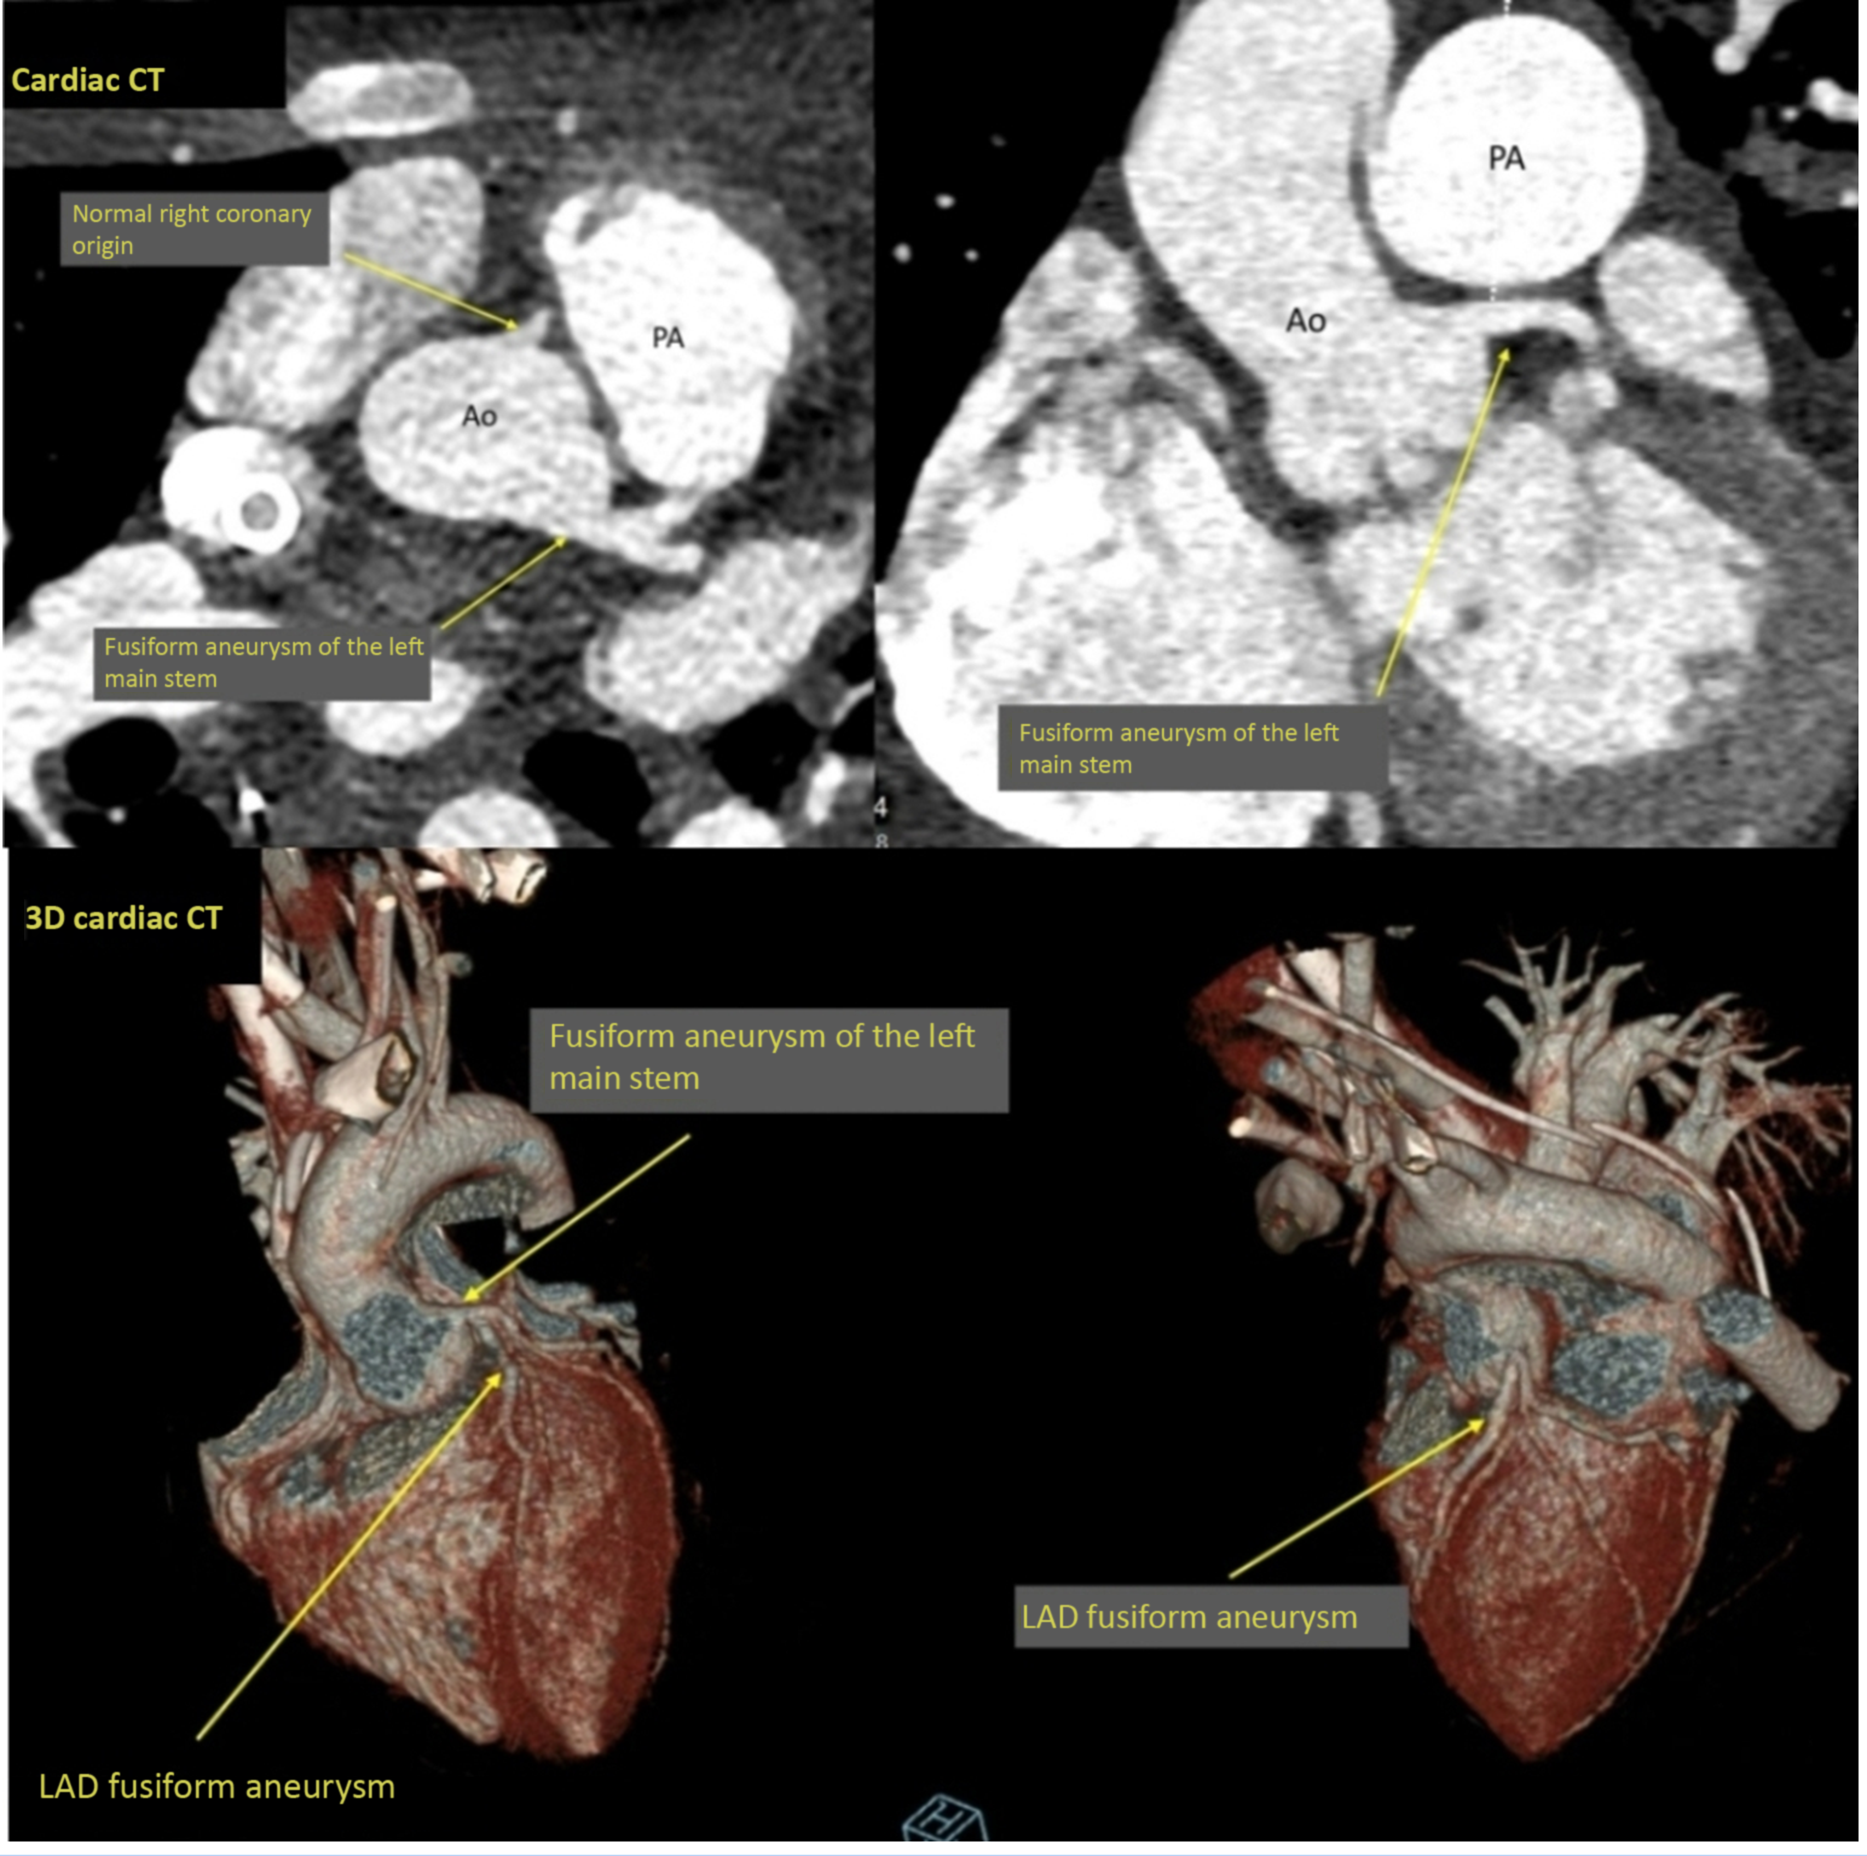

Transthoracic echocardiography immediately following paediatric ICU admission showed a structurally normal heart with severely impaired biventricular systolic function with left ventricle fractional shortening of 10%. Kawasaki disease shock syndrome was considered, and echocardiography showed bright but non-dilated coronary arteries. However, cardiac CT performed on day 4 showed a small fusiform aneurysm of 4.2 mm (Z score +2.6 Reference Dallaire and Dahdah1 ) of the entire length of left main stem and a fusiform aneurysm of 3.5 mm (Z score +3.0) of the proximal and middle segments of the left anterior descending (Fig 1). Chest CT showed extensive bilateral patchy consolidation and adjacent ground glass opacification affecting all lobes with a lower lobe predominance. The main pulmonary artery was dilated with no visualised pulmonary embolism (Fig 2).

Figure 1. Cardiac CT showing fusiform aneurysm of the left main stem and normal right coronary origin. Ao = aorta, PA = pulmonary artery. 3D Cardiac CT showing fusiform aneurysm of the left main stem, LAD fusiform aneurysm. LAD = left anterior descending.

In this case, cardiac CT was performed to delineate coronary anatomy which was not clearly seen on transthoracic echocardiography due to the poor lung acoustic windows from the underlying severe lung disease. An ECG-gated cardiac CT was performed using Siemens SOMATOM Force. And 2 ml/kg omnipaque was injected at 2 ml/s and monitoring slices at the mid-descending aorta were used to time maximal contrast opacification of the vessel. A single end-systolic time frame was acquired in expiration with the extracorporeal membrane oxygenation circuit clamped for the duration of the injection.

Coronary artery aneurysms were identified on cardiac CT, despite the initial absence of obvious dilatation on transthoracic echocardiography scans. This emphasises the value of cardiac CT to confirm or rule out coronary artery involvement particularly in extremely sick children with severe myocardial dysfunction and elevated cardiac biomarkers. While echocardiography measures the coronary artery dimension in a single plane, cardiac CT has the advantage of permitting orthogonal imaging of the vessel. Reference Ghekiere, Salgado and Buls12 CT demonstrated that the vessel dimension was found to be enlarged in a tangential dimension to that measured by echocardiography. Furthermore, although initial echocardiographic imaging suggested no aneurysm of the coronary arteries, imaging was limited to only the most proximal coronary segments due to poor acoustic windows and reduced ultrasound penetrance. In contrast, CT is able to show distal coronary artery anatomy with a high degree of spatial resolution. This highlights the use of echocardiography as a screening tool and the additional benefits of performing cardiac CT in those who are most unwell or with the highest suspicion of coronary anomalies. MRI was also able to define the proximal aneurysms but did not have the necessary spatial resolution to define the extent of the aneurysms more distally.